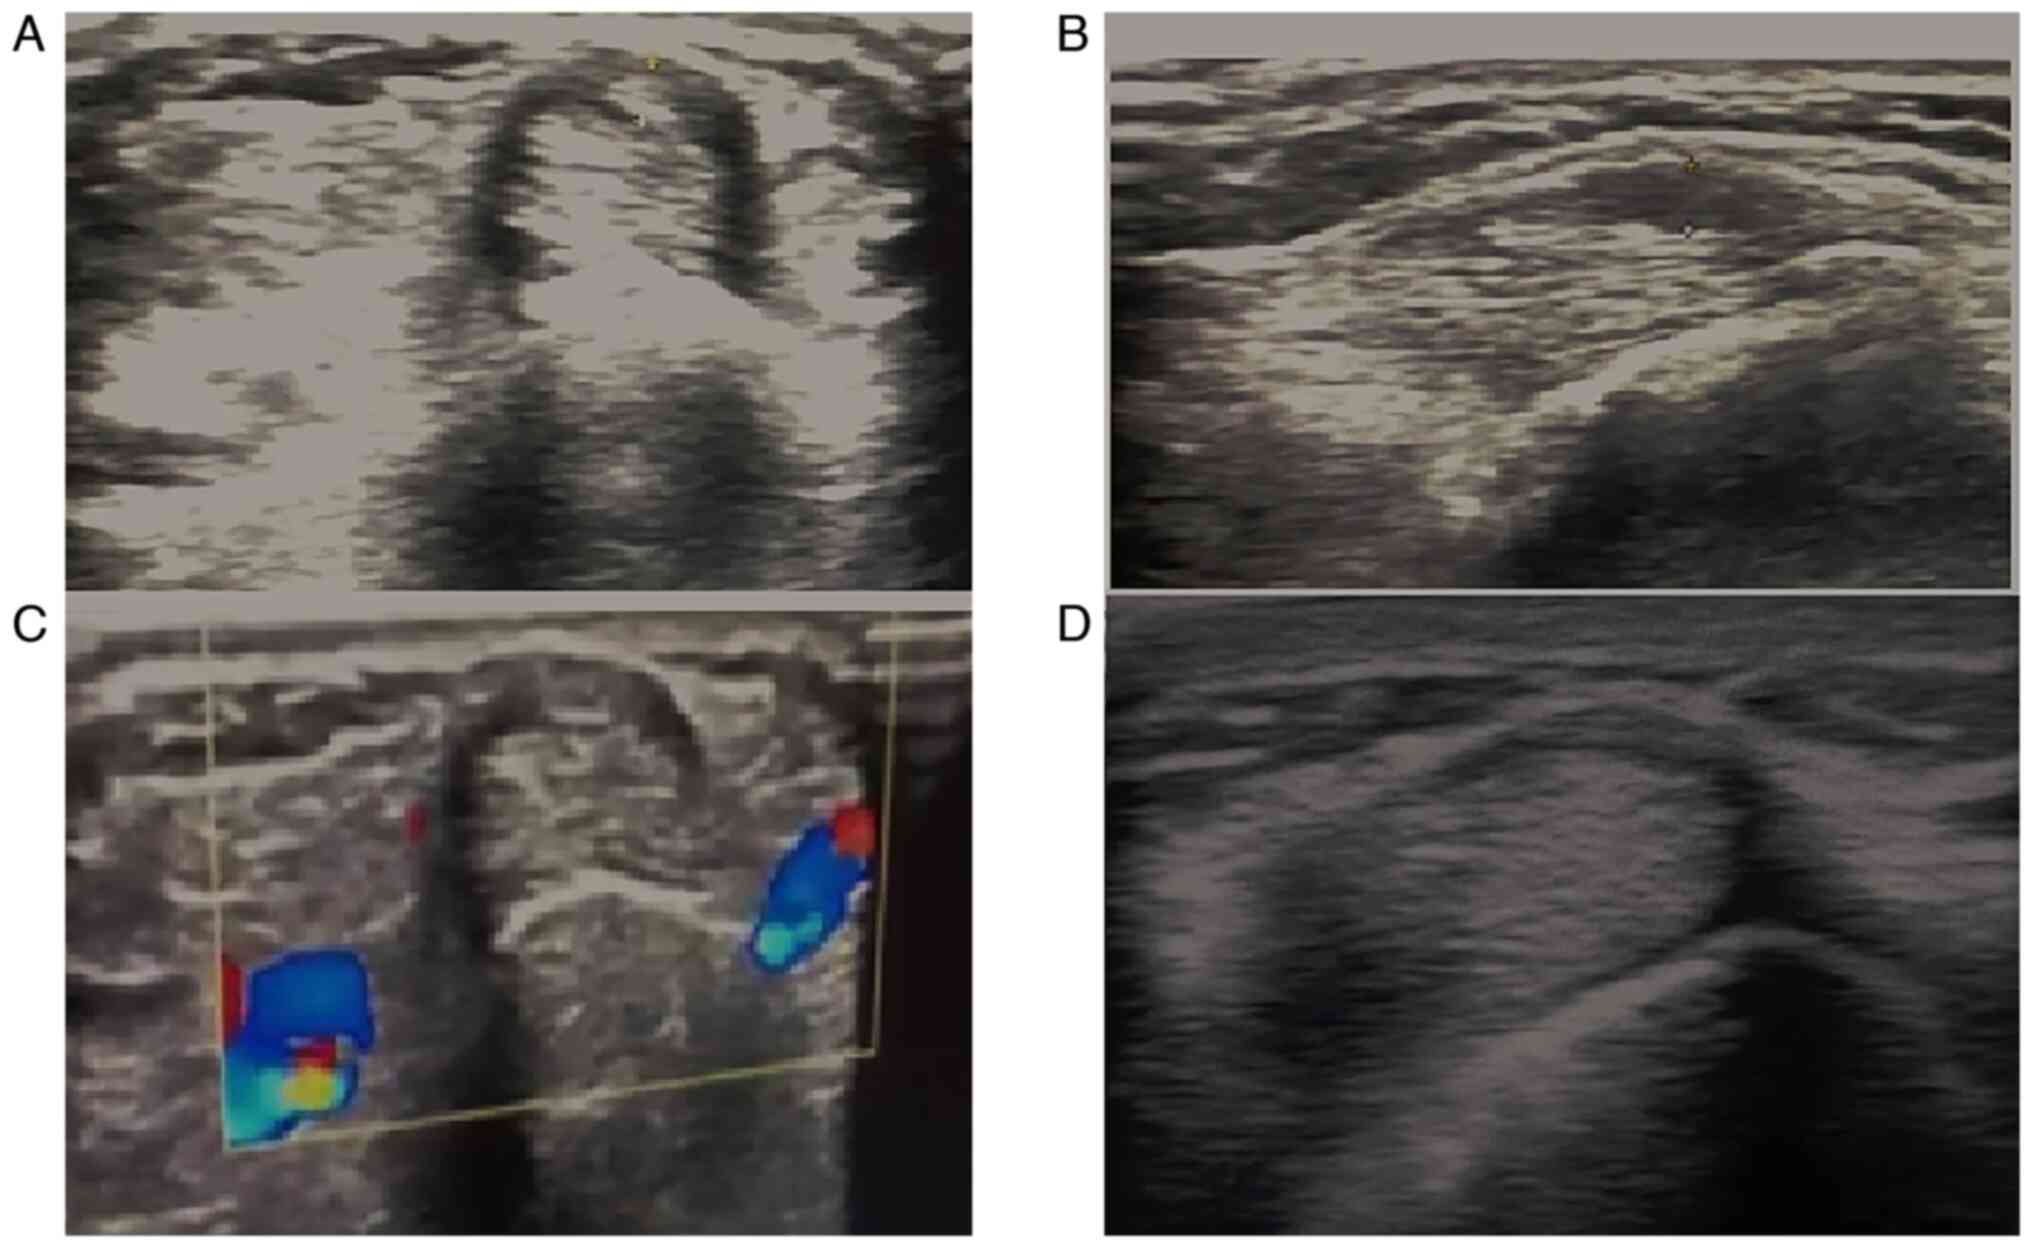

Baseline sonographic findings (as presented in Table III) revealed a thickened retinaculum (1.89±0.5; ranging from 1.3-3 mm) and tendon sheath effusion (2.07±0.52) in all patients (illustrated in Figs. 1 and 2). As regards anatomical variations, 5 patients (41.7%) had septum between APL and EPB, and 4 patients (33.3%) had accessory tendon slips (example illustrated in Fig. 1). However, post-PRP injection, a US examination at the 1- and 3-month follow-up periods revealed a significant improvement in the patients. The thickness of the extensor retinaculum had progressively decreased, from a mean of 1.89 mm pre-injection to a mean of 1.3 mm and 0.96 mm at the 1- and 3-month follow-up, respectively (P<0.001). The tendon sheath effusion observed in all the patients had a mean thickness of 2.07 mm pre-injection. At the 1-month follow-up, effusion was observed in 11 cases (91%) with a mean thickness of 1.6 mm, and at the 3-month follow-up, only 7 of the cases had effusion (58%) with a mean thickness of 0.73 mm (P<0.001). Peri-tendinous hyperemia was initially observed in 7 patients (58.33%), and after the PRP injection this was only observed in 2 patients (16.7%) at the 1-month follow-up (P<0.063) and in no patients (0%) (P<0.001) at the 3-month follow-up (Table III; examples illustrated in Fig. 3). Sonographic improvements observed in two different patients are illustrated in Figs. 4 and 5.

Figure 1

Transverse scan of the first dorsal compartment showing thickened retinaculum (red arrow), with tendon sheath effusion (blue arrow).

Transverse scan of the first extensor compartment: (A) Normal hand compared to (B) symptomatic hand with tendon sheath effusion and (C) a hand with a thickened retinaculum.

Figure 3

Transverse scan of the first extensor compartment of two different patients (top and bottom panels), illustrating peri-tendinous hyperemia, a thickened retinaculum and tendon sheath effusion.